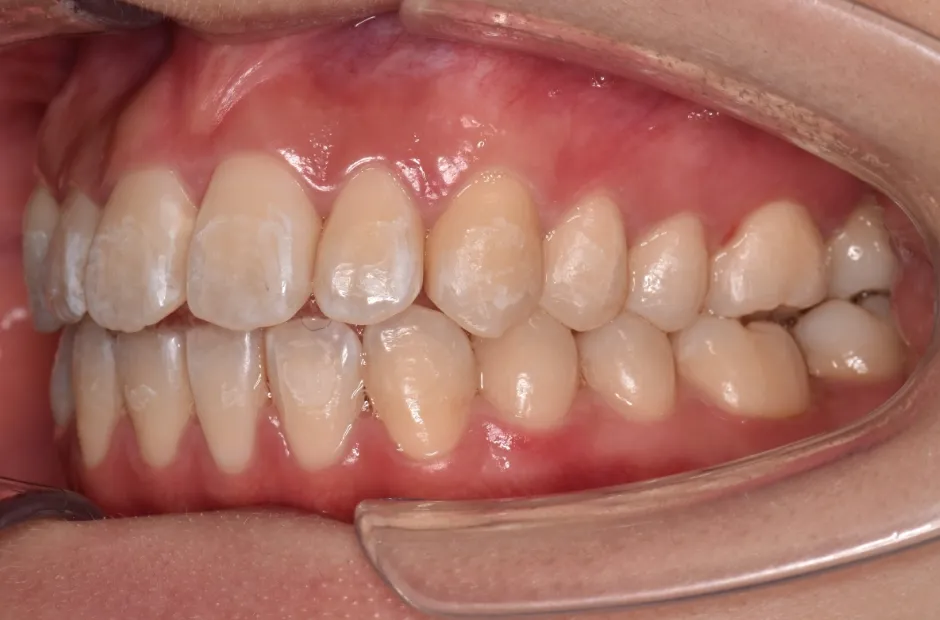

前歯部反対咬合

| 診断名・主訴 | 前歯部反対咬合 |

|---|---|

| 年齢・性別 | 14歳・男性 |

| 治療期間・回数 | 1年2か月 |

| 治療に用いた主な装置 | ブラケット矯正 |

| 抜歯部位 | なし |

| 治療費 | 60万円(税抜) |

| リスク・副作用 | 装置による違和感・疼痛・歯肉退縮・歯根吸収・虫歯のリスクなど |

治療前

治療後